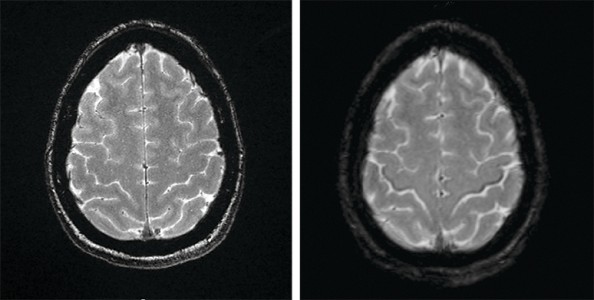

Susceptibilitetsvektede MR-bilder (SWI-magnitude) av hjernen (bildet til høyre) viser lavsignal forenlig med jernavleiring i bakre deler av gyrus precentralis tilsvarende motorisk korteks på begge sider hos en pasient i 50-årene med amyotrofisk lateral sklerose (ALS) (1, 2). Det såkalte svart bånd-tegnet (motor band sign / black ribbon sign) synes ikke på MR-bildene tatt ett år tidligere (bildet til venstre).

Ved utredning av mistenkt amyotrofisk lateral sklerose har MR-undersøkelse til nå blitt brukt differensialdiagnostisk med tanke på andre årsaker til øvre motornevrontegn (for eksempel cervikal myelopati og cerebrovaskulære forandringer). Kasuistikken illustrerer at magnetisk resonanstomografi kan vise spesifikke funn ved amyotrofisk lateral sklerose, som jernavleiring i gyrus precentralis. I en prospektiv studie fra Mexico hadde 92 % av 38 ALS-pasienter «svart bånd-tegn» på tre tesla-MR-undersøkelser (1). Ved Oslo universitetssykehus har vi fra 2020 begynt å gjøre MR med SWI-sekvenser rutinemessig ved utredning av amyotrofisk lateral sklerose.